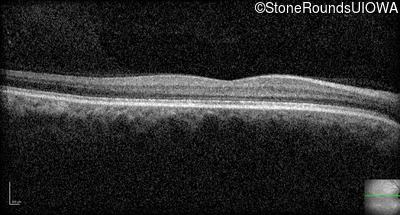

Optical Coherence Tomography - Right - 20/160 -1

Exemplar / OCT Stack